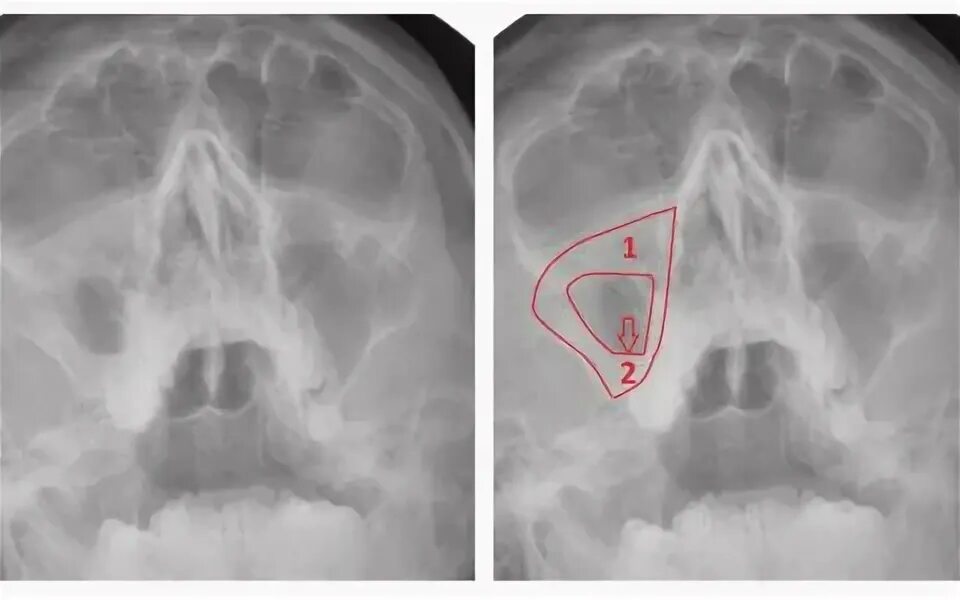

Утолщение верхнечелюстной пазухи что это значит